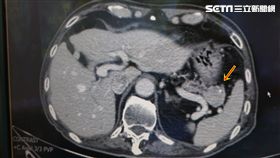

成因不明、無從預防 翁罹賈伯斯病

蘋果電腦創辦人賈伯斯罹患胰臟神經內分泌瘤,因此這個疾...

2017/09/07 10:19